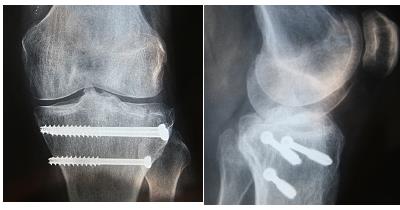

Saubere Arbeit, da war ein fähiger Handwerker am Werk -

Schönes Foto, das hat eine fähige MTA geschossen sfg

Solange die Schrauben nicht locker sind, können sie noch drinbleiben...